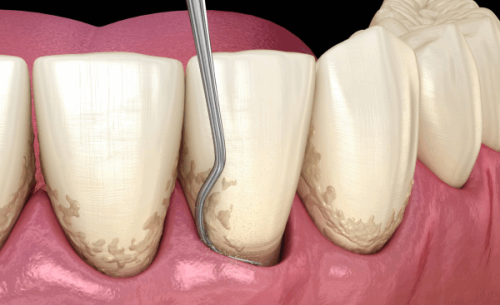

商丘交通医院中韩口腔可开展的诊疗项目丰富多样,包括种植牙、即刻种植、牙齿错颌畸形矫正、隐形矫正、儿童早期功能性矫治、牙齿美白、嵌体修复、烤/全瓷牙修复、可摘局部义齿、全口假牙、套筒冠义齿、覆盖义齿牙周治疗等项目。 医院在开展各项诊疗项目时,严格遵循国内外标准和规范,确保治疗成效和安心性。例如在种植牙手术中,医院采用精良的种植技术和设备,从种植体的选择、种植手术的操作到术后的护理和随访,都有一套严格的流程和标准,以确保种植牙的成功几率和使用寿命。 在牙齿矫正方面,医院根据患者的年龄、牙齿情况和个人需求,制定出个性化的矫正方案。无论是青少年还是成年人,都能够在商丘交通医院中韩口腔找到适合自己的矫正方法,实现牙齿的整齐美观。

商丘交通医院中韩口腔十分注重消毒工作,严格按照国内卫生标准和规范进行操作,确保看牙的无菌环境。 医院的诊疗室设计为一个个挨着的半隔间,医生看诊整齐有序。每个诊疗室都配备了独立的消毒设备,医生在为患者看诊前,会对诊疗室进行全方面的消毒,包括桌椅、医疗器械、地面等。 同时,医院还采用了精良的消毒技术和方法,如紫外线消毒、高温高压消毒等,对医疗器械进行完全的消毒灭菌,确保医疗器械的安心性和卫生性。此外,医院还要求医护人员在操作过程中严格遵守无菌操作原则,佩戴口罩、帽子、手套等防护用品,防止交叉感染。